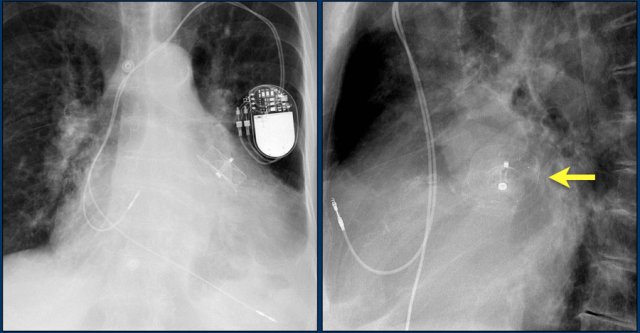

The image is taken immediately after placement of an ICD.

There is a small pneumothorax (arrow).

This is the most common complication.